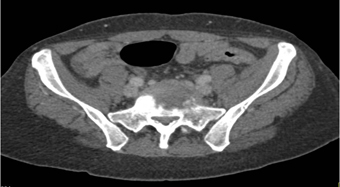

The best diagnosis in patient with left hip pain is?

sacral fracture

psoas bleed

osteomyelitis at L5-S1

metastases to L5 and S1